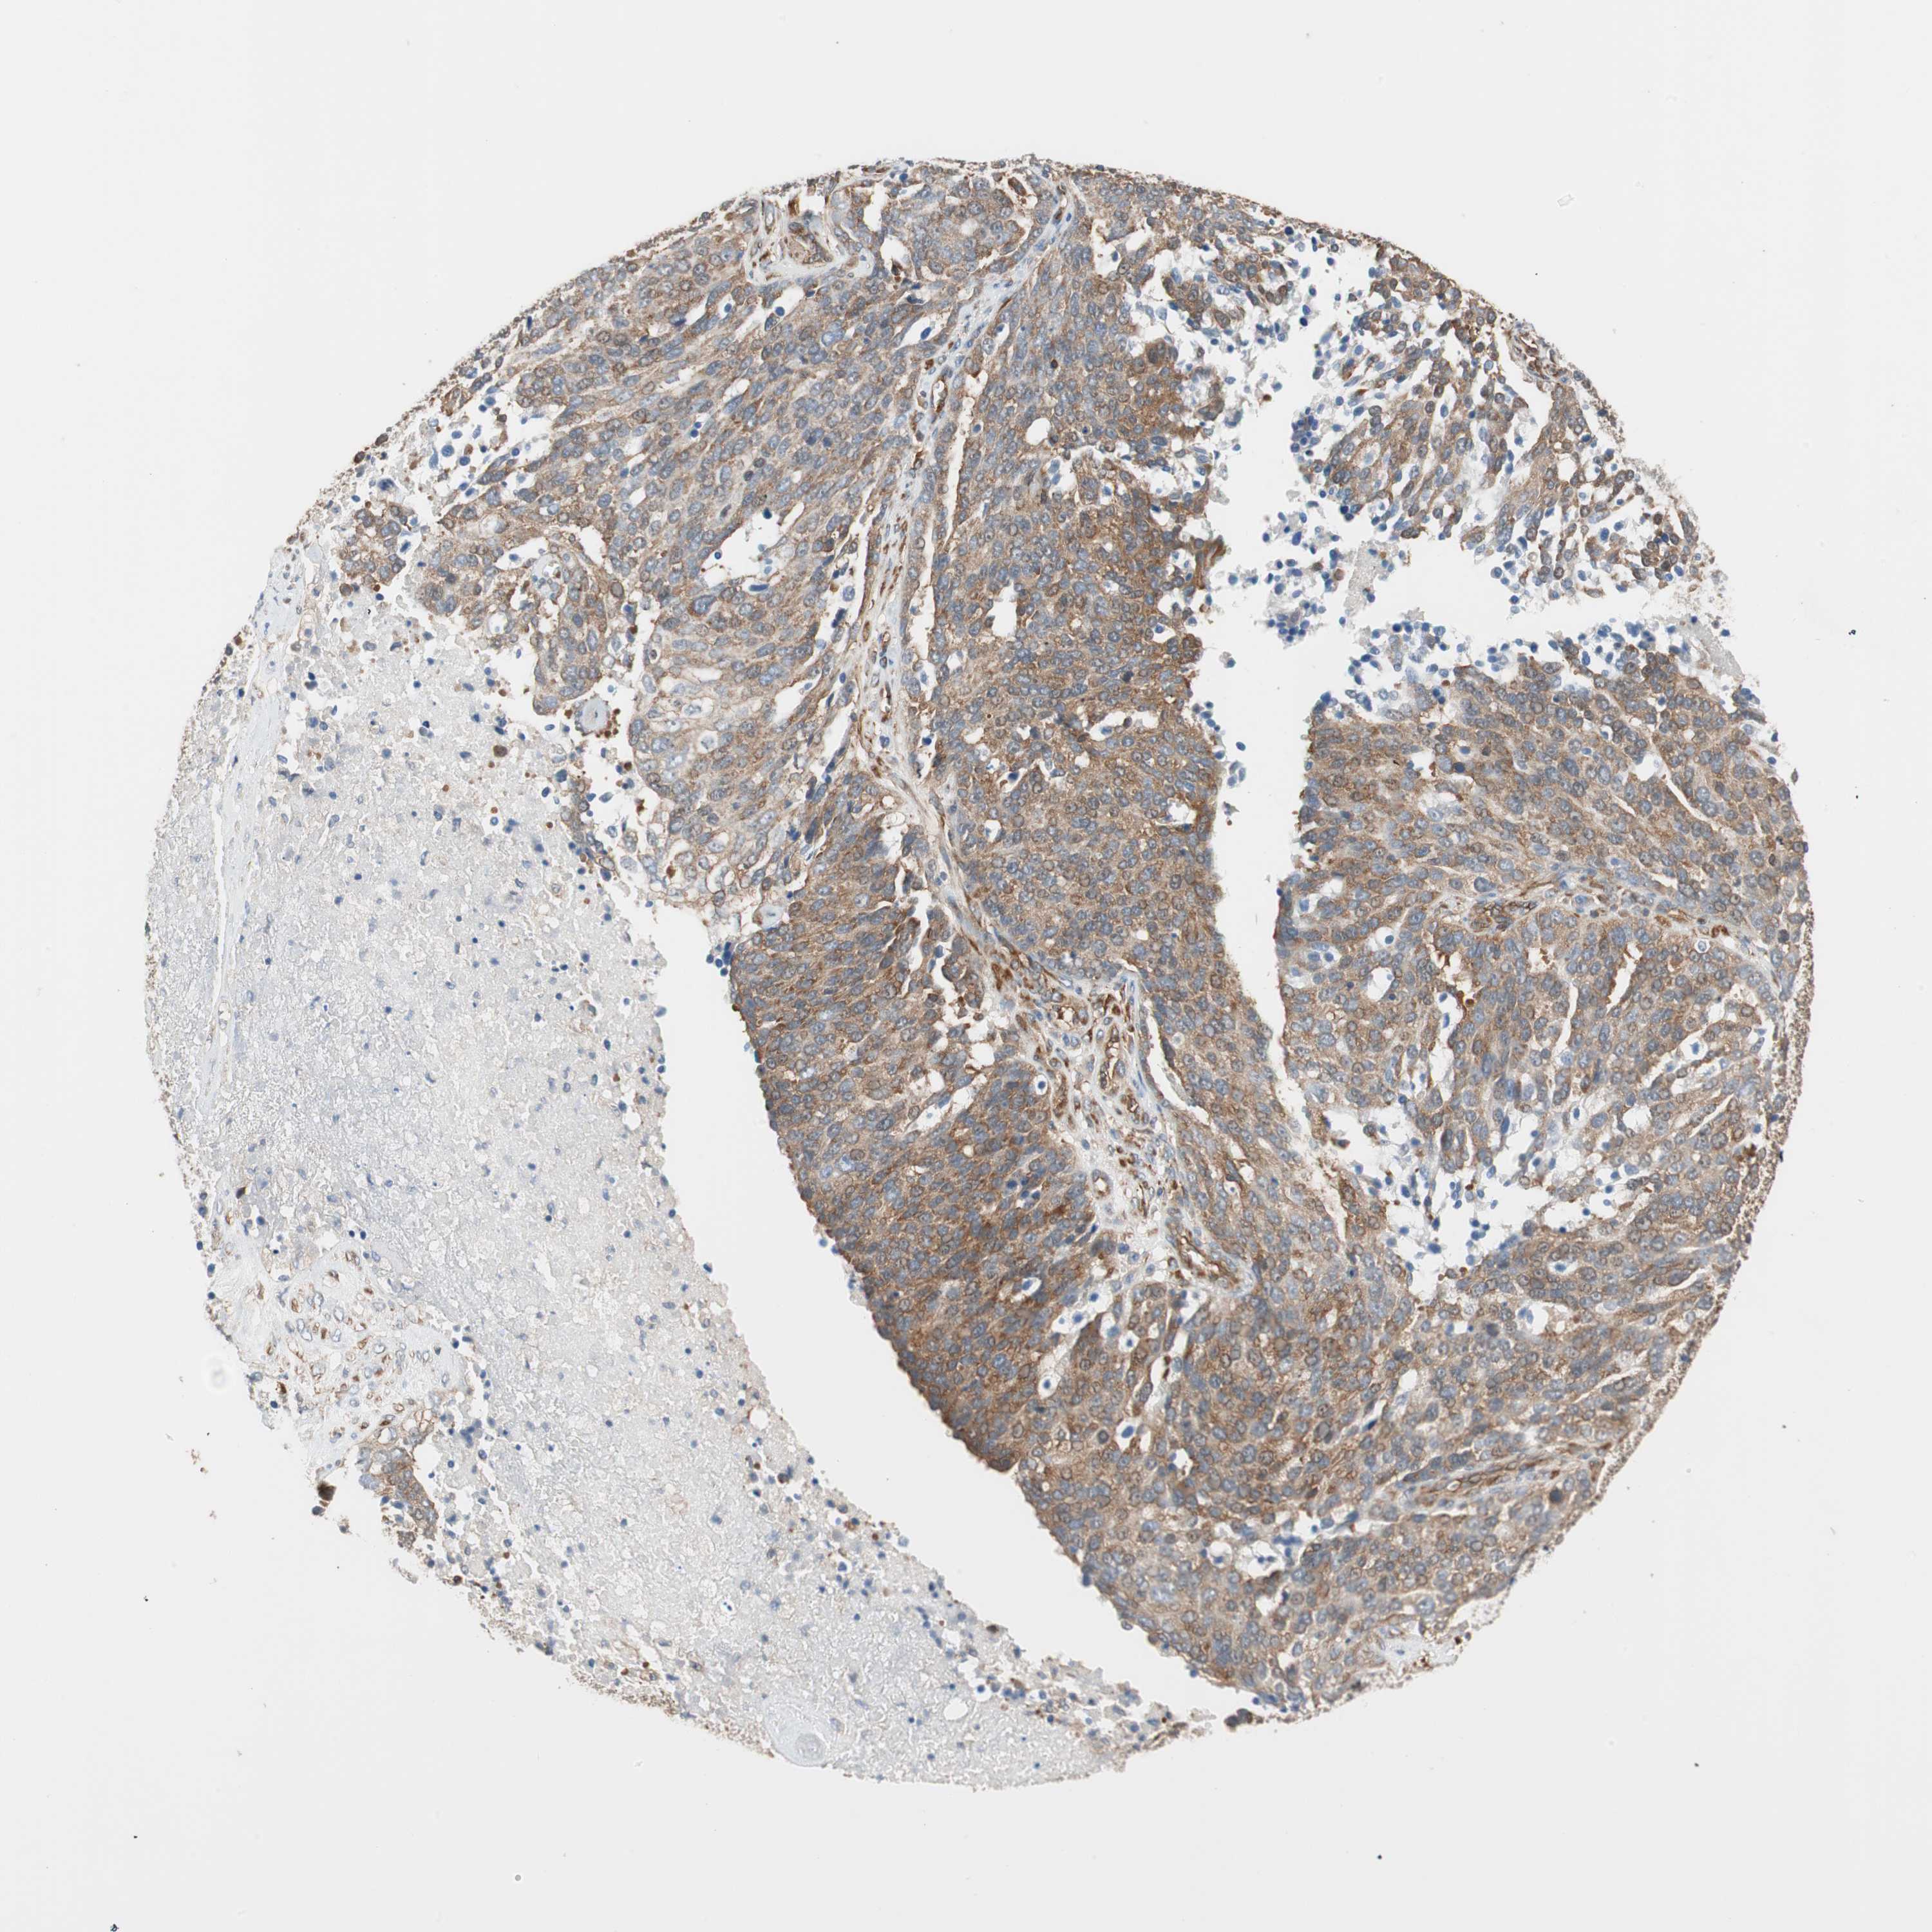

OVARIAN CANCER - Protein expressioni

A mouse-over function shows sample information and annotation data. Click on an image to view it in a full screen mode. Samples can be filtered based on level of antibody staining by selecting one or several of the following categories: high, medium, low and not detected. The assay and annotation is described here.

Note that samples used for immunohistochemistry by the Human Protein Atlas do not correspond to samples in the TCGA dataset.

Antibody stainingi

Antibody staining in the annotated cell types in the current human tissue is reported as not detected, low, medium, or high, based on conventional immunohistochemistry profiling in selected tissues. This score is based on the combination of the staining intensity and fraction of stained cells.

Each image is clickable and will lead to virtual microscopy that enables deeper exploration of all samples and also displays staining intensity scores, fraction scores and subcellular localization as well as patient and tissue information for each sample.

Antibody HPA005750

Antibody CAB005399

Cystadenocarcinoma, serous, NOS

Carcinoma, endometroid

Cystadenocarcinoma, mucinous, NOS

Carcinoma, NOS